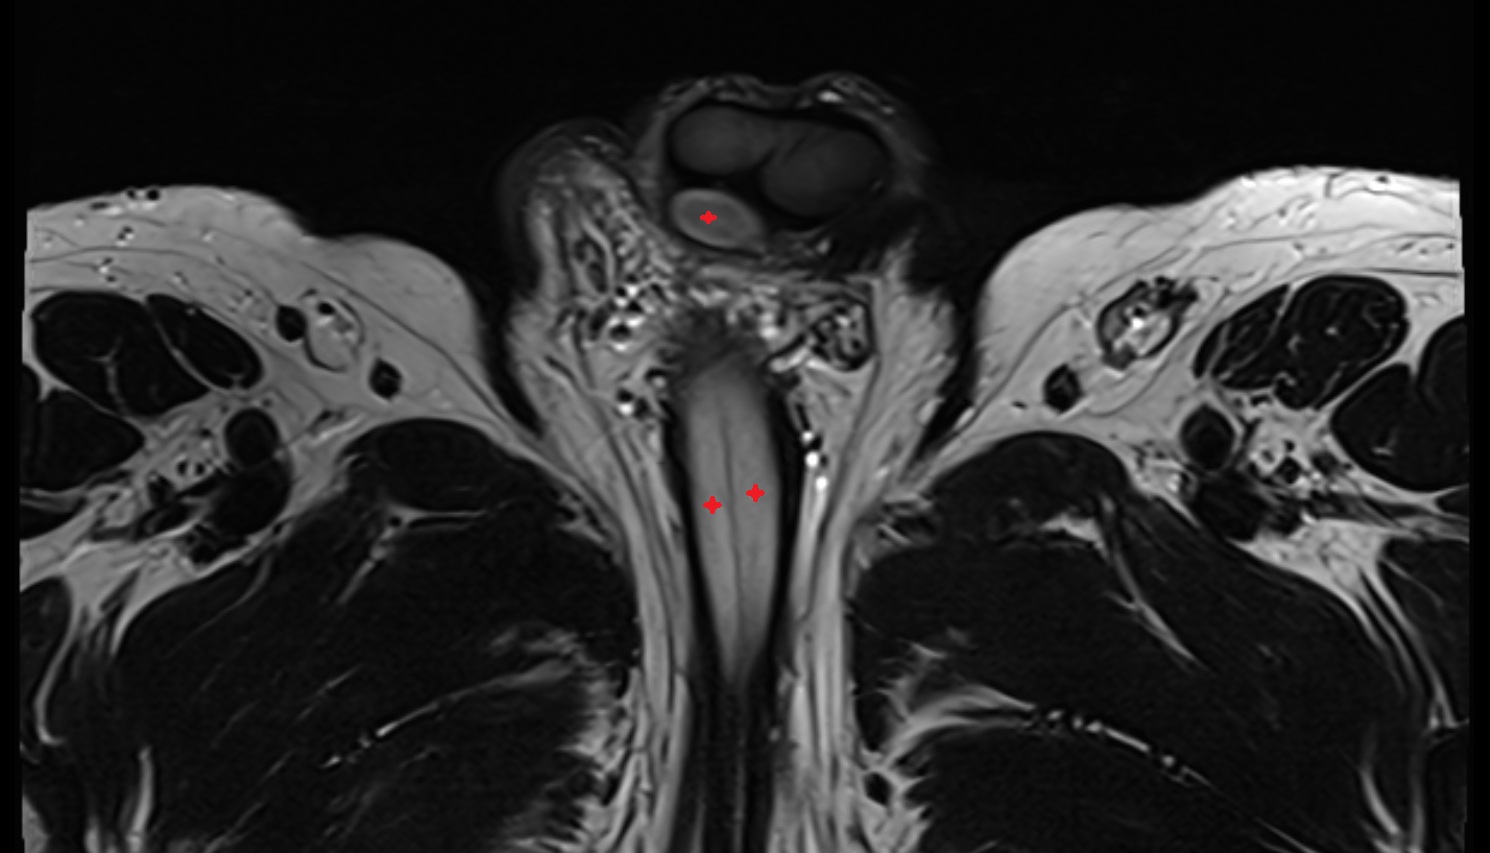

- Corpus cavernosum

- Corpus spongiosum

- Bulb of Penis

- Crus of penis